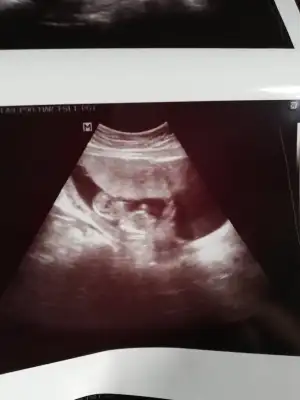

Sanki kız gibi eminde olamadım

Kız gibi gibi diyorum net değil usg başka varsa paylaşın emin olamadım12+4 günlük yorumlayabilir misiniz![]()

Sanki kız gibi ama emin değilim nubu karanlık kalmış 12 yada 13 haftada paylaşın emin olmak istiyorum![]()

Maalesef başka ultroson fotoğrafı yok. Kontrole gidersem atarım. TeşekkürlerKız gibi gibi diyorum net değil usg başka varsa paylaşın emin olamadım![]()